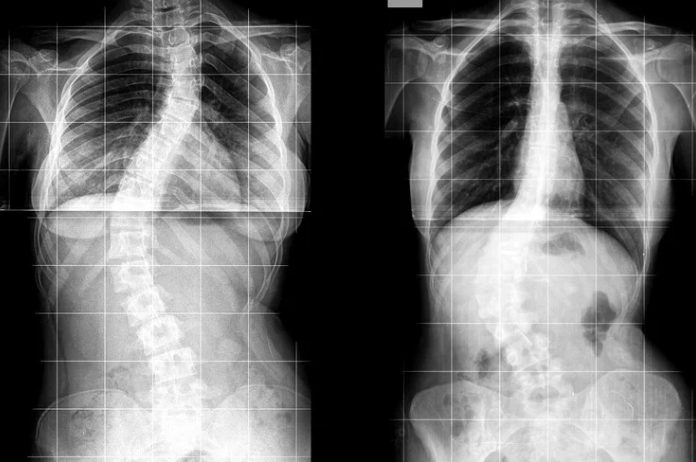

Scoliosis is a condition that causes the spine to curve sideways, often in an “S” or “C” shape. While it may sound serious, many people have mild scoliosis without even realizing it. That’s why recognizing the early signs of scoliosis is so important. The sooner it’s identified, the easier it is to monitor and manage, especially with help from a skilled chiropractor.

Scoliosis refers to an abnormal lateral curvature of the spine. Instead of running straight down the middle of the back, the spine curves to the side, sometimes just slightly, and in other cases more significantly.

How Is Scoliosis Diagnosed?

If scoliosis is suspected, we may refer you for an X-ray to confirm the diagnosis and measure the degree of curvature (called the Cobb angle). From there, we’ll tailor a care plan based on your specific needs.